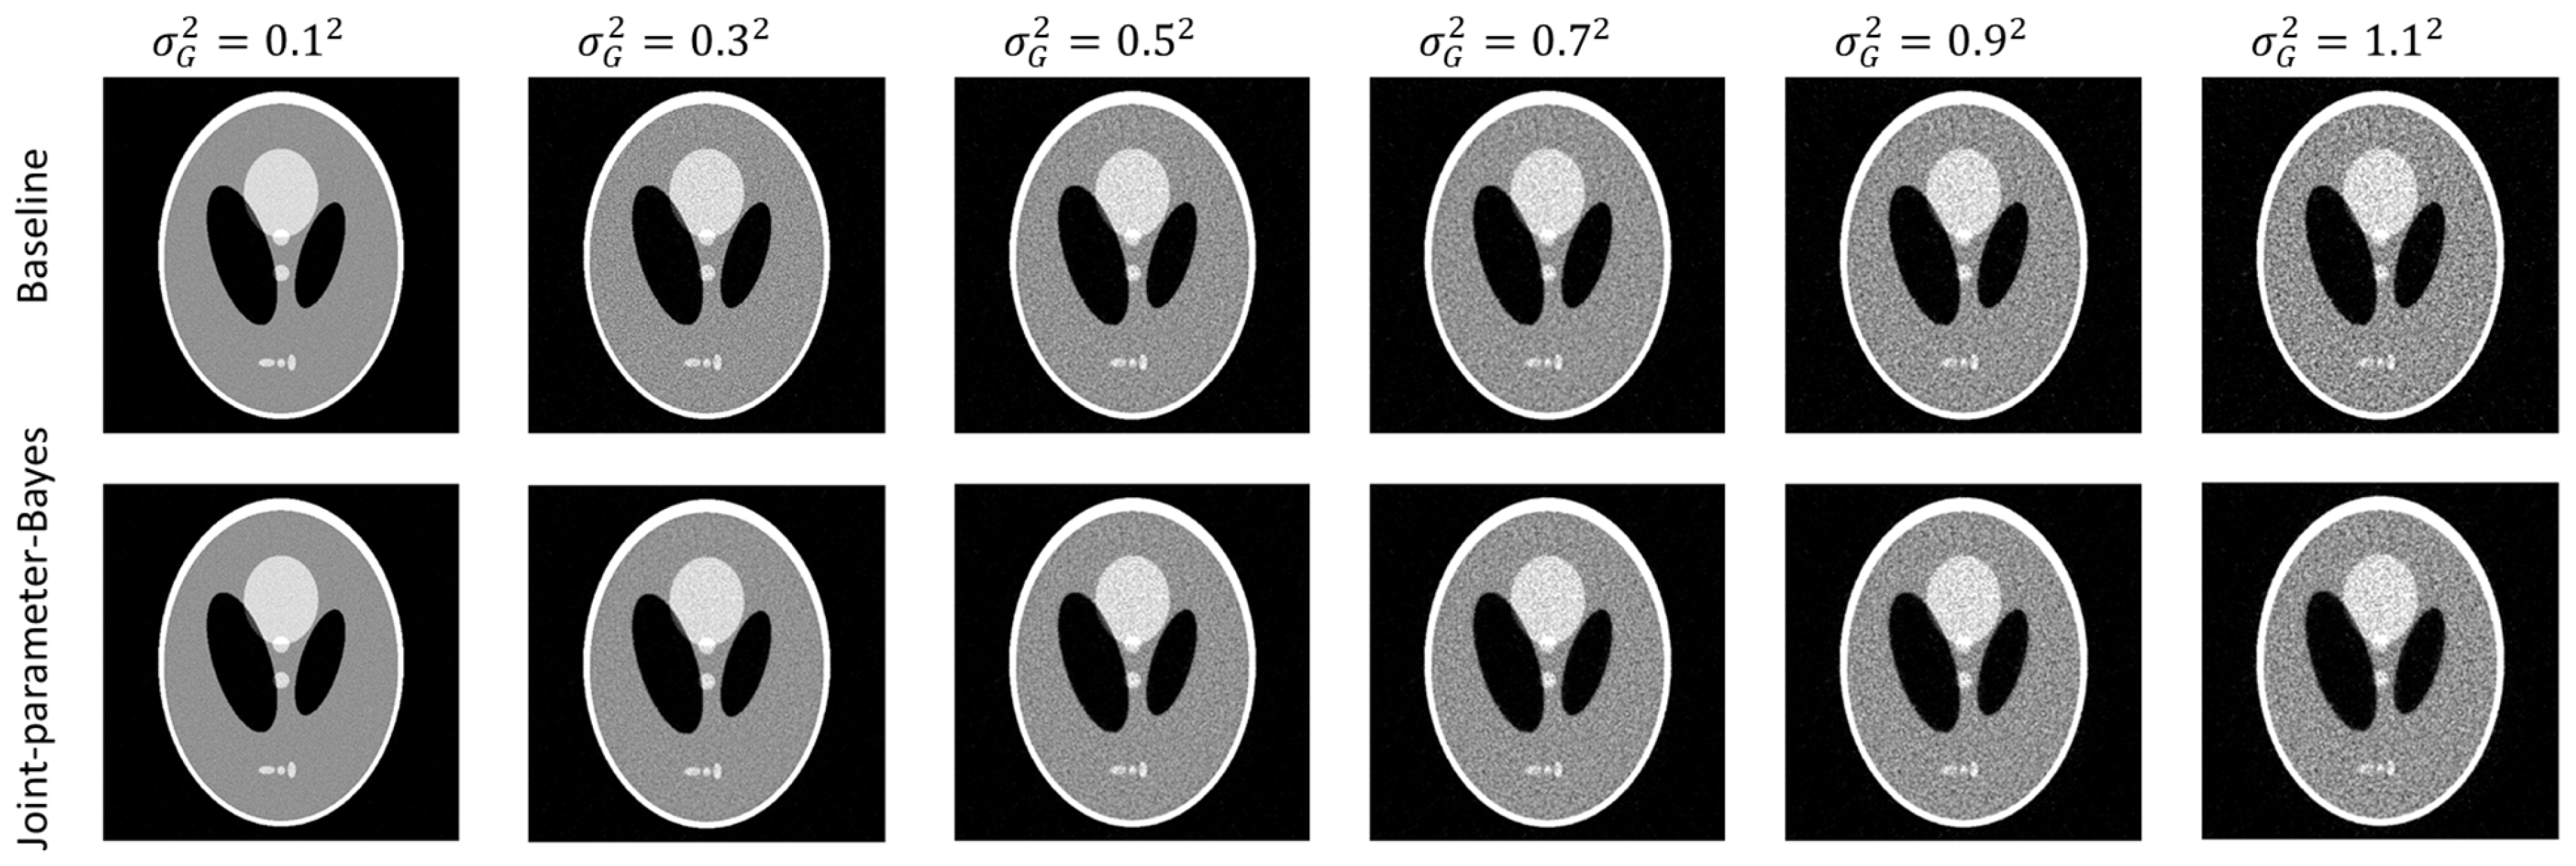

As described in Section 2.3, the stopping position (i.e., different number of iterations) may result in different image quality. In this section, we investigate the stopping criterion for the proposed joint-parameter-Bayes by exploring the correlation between the two unobservable parameters and image quality. To see the response of the stopping criterion to different noises, three noise types mentioned above are added to the simulation data, including white Gaussian noise to post-log sinogram data, Poisson-like signal-dependent noise to post-log sinogram data, and Poisson noise to the pre-log transmission data. As introduced in Section 3.1.1, we can manipulate the variance to mimic different noise levels for white Gaussian noise. For Poisson noise to sinogram data, we scale the values of Shepp–Logan phantom by different factors and then add Poisson noise to its sinogram data from forward projection. By doing so, we can mimic different noise levels by varying the factor value. Three scaling factors are used, which are 1, 5 and 10. For the Poisson noise to transmission data, it is more like the realistic noise model introduced in Section 2.1.1. By varying the incident flux , we simulated different noise levels. In this work, we chose five incident flux, .

Figure 4 shows the change of two unobservable parameters along with their iteration. The image quality measure RMSE is also plotted in the same figure to find some correlations. It can be found the unobservable parameter has a coincident turning point with the optimal image quality. For example, in the case of , the image quality (red line) has a valley around 250 iterations. The curve has a very fast drop at several iterations and then becomes flat. The curve has a relatively slow drop and then becomes flat. If we call the largest slope rate change point the turning point, the turning point of image quality and are almost identical. Therefore, we can monitor the transformation of along with iteration and terminate the reconstruction at its turning point, since the image quality measure RMSE cannot be obtained in real cases. For the other two noise types, the above observations are found in the case of scale factor = 1. The change of remains the same, but the curve decreases first and then increases. Interestingly, the image quality also deteriorates first and then improves. After the changing point, both image quality and tend to converge. One possible reason for the initial un-monotonic tendency could be the initial condition. This effect can be removed, however, if we start to monitor the value of several iterations (e.g., 10 iterations) late. After the removal of the initial effect, the regulations can be summarized as if decreases monotonically, the reconstruction can stop at the turning point, and if increases, the reconstruction can stop when it is converged. It is interesting to find that the prior variance parameter t has such an explicit correlation with the image quality. Data variance parameter s has no such clear tendency. One possibility could be that the prior variance t is directly related to the image domain and data variance parameter s is directly related to the measurement. Therefore, the relationship between image quality and t is not explicit. It is also noted that the t curves have different patterns under different noise conditions, regardless of the initial effect. This is expected because the data-independent, data-dependent and logarithm non-linearity type noises are introduced on purpose. The three noise types cover the most popular models used in the image reconstruction. Based on the observation, we find some semi-experimental regulation of the early stop criteria for optimal image reconstruction. To fully understand the curve patterns under different noise conditions is one of our future research interests.

Figure 4.

Stopping criterion under three different noise types. The change of two unobservable parameters () and change of image quality (RMSE) along with iteration are plotted.

In the experiments, it is noticed that the stopping criterion should be part of the joint-parameter-Bayes method. Ignoring the stopping criterion may result in unsatisfying results. We presented the reconstructed images of early stop criterion and hard threshold in Figure 5. We can see that the early stop can produce better reconstructed images.

Figure 5.

Reconstructed images by FBP (left column) and the joint-parameter-Bayes method with early stop (middle column) and hard threshold stop (right column). The display window is [0, 0.035] mm−1.